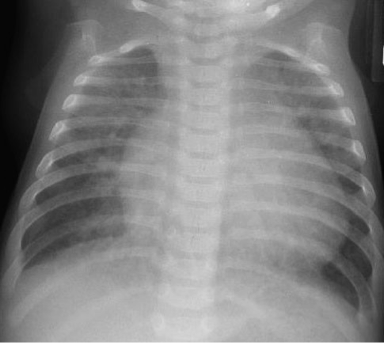

- A chest radiograph: cardiomegaly, narrow mediastinum, and increased pulmonary vasculature. ECG: RAD and RVH